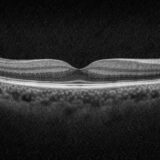

OCTとは?解析レポートの見方と活用ポイントを解説

CIRRUS OCTのGanglion Cell解析を徹底解説|GCL+IPLの意味とレポートの見方